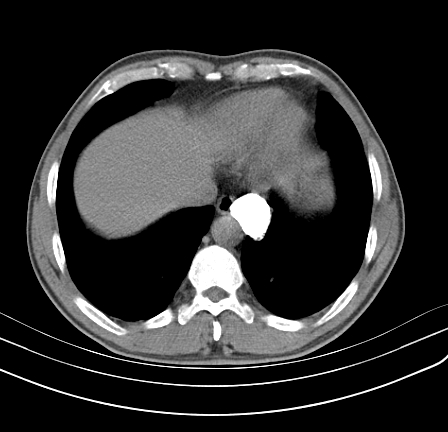

以下是引用影像孺子牛在2009-5-20 23:18:00的发言:[br]左侧后心膈角处类椭圆形钙化灶,最常见的是淋巴结钙化,但太大了不支持,其它如食管囊肿钙化、实性畸胆瘤等。何东西钙化真不好定。

以下是引用zbp537在2009-5-20 20:52:00的发言:[br]钙化灶,来源不好说。